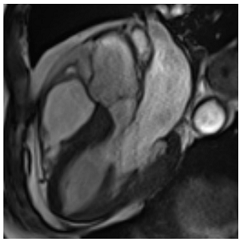

Table 3 summarises a suggested CMR scan protocol for the diagnosis of presumed HHD and differential diagnosis of patients with a “thickened left ventricle”.

Table 3.

The cardiovascular magnetic resonance protocol used for assessment of hypertensive patients. The described protocol can be acquired within 45–50 min. Images are examples from patients with hypertensive heart disease.

To avoid the low but important risks of endomyocardial biopsy, which can have an overall complication rate of up to 6% [2], myocardial fibrosis can be assessed non-invasively using CMR: LGE is suitable for detecting irreversible replacement fibrosis and myocardial scarring and T1/ECV mapping for detection of potentially reversible (reactive) interstitial and more diffuse fibrosis (not detectable by LGE) (Figure 2).

9. Tissue Characterisation with Late Gadolinium Enhancement

LGE has become the reference standard for non-invasive imaging of myocardial scar and focal fibrosis [40]. Gadolinium chelates are interstitial agents that cannot penetrate healthy intact cell membranes. Therefore, they remain in the interstitial space and accumulate in areas of cell injury/necrosis and focal fibrosis where this is expanded, while in healthy regions, contrast more readily washes out [41]. Specific LGE patterns are seen in different diseases (e.g., subendocardial fibrosis in CAD, patchy epicardial/mid-wall fibrosis in areas of hypertrophy in HCM). Minor areas of LGE can be detected in up to 50% of patients with HHD, but there is no specific pattern (in 95% of the non-ischaemic LGE distribution) [42]. If present, LGE is often found in the basal to mid-septal, inferior, and inferolateral segments in patients with HHD [42]. The severity of diastolic dysfunction increases with the extent of fibrosis by LGE [25,31]. Furthermore, focal fibrosis/LGE may be a substrate for ventricular arrhythmia and is associated with sudden cardiac death [31].